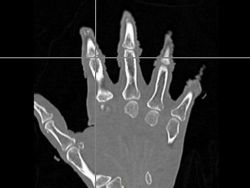

- The first was that we have integrated a rigid body initialization for a Thirion Demons registration for atlas <-> subject registration. The above modification was used to warp the atlas to the subject as shown in the figures.